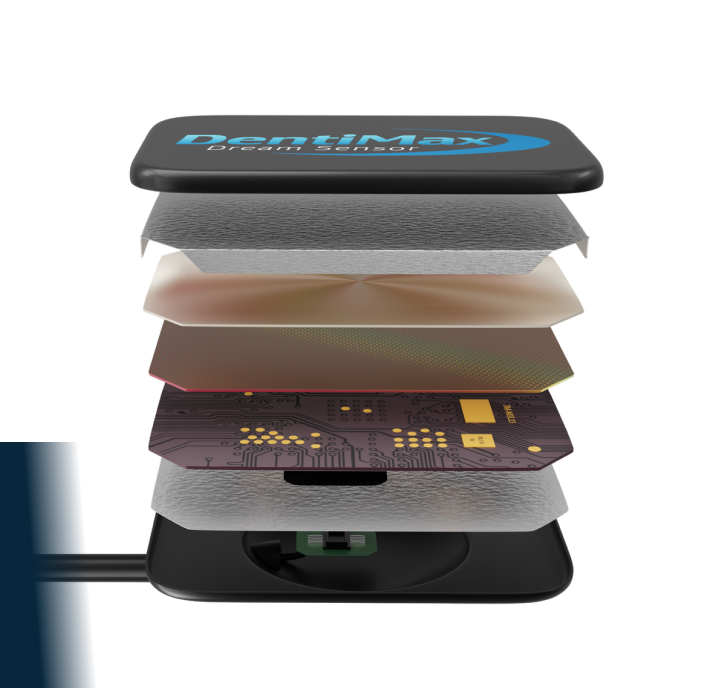

Our award-winning Dream Sensor is one of the top-rated digital x-ray sensors in the dental business by clinicians. Offering unbeatable image quality, superb dependability, and ultimate patient comfort – there’s a reason it’s one of the best-selling dental x-ray sensors on the market.

- Thinnest CMOS on the market (5.3mm)

- Waterproof sealed housing

Product Specifications:

| Size 1 | Size 2 | |

|---|---|---|

| Active Area | 19.95mm x 30.02mm | 25.99mm x 36.00mm |

| Sensor Plate Thickness | 5.3mm | |

| Resolution | 20 line pair/mm actual, 26.3 line pair/mm theoretical | |

| Pixel Size | 19 Microns x 19 Microns | |